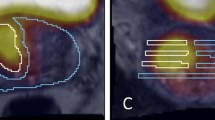

Alternative methods include three-dimensional quantification based on an ellipsoid formula or plainmetry. Planimetric volume measurement is presumed to be the most accurate technique and the majority of studies evaluating mp-MRI-derived tumour volumes adopt this approach. Plainmetry requires contouring of the lesion on each axial slice and places a significant additional time burden on the reporting radiologist.

At present, there remains no agreed method of measuring tumour volume on mp-MRI. Plainmetry is not routinely used in clinical practice although there is potential for this to change with further research into semi-automated or fully automated volumetric measurement software [51]. This issue was discussed in a recent expert consensus meeting and the panel concluded that there was not sufficient evidence to recommend any optimal method for measuring tumour volume on mp-MRI [52].

Cornud et al. [35] recommended a ‘target volume’ calculated on the largest tumour area on each axial slice from any sequence, but this resulted in an overestimation of pathological tumour volume by 44%. Recent work has attempted to quantify this into an exact margin using a simulated cylindrical treatment volume or the widest margin to achieve complete histological tumour distribution in all patients. These different methodologies have produced variable results with margins ranging from 5 mm [33] up to 13.5 mm [41, 55].